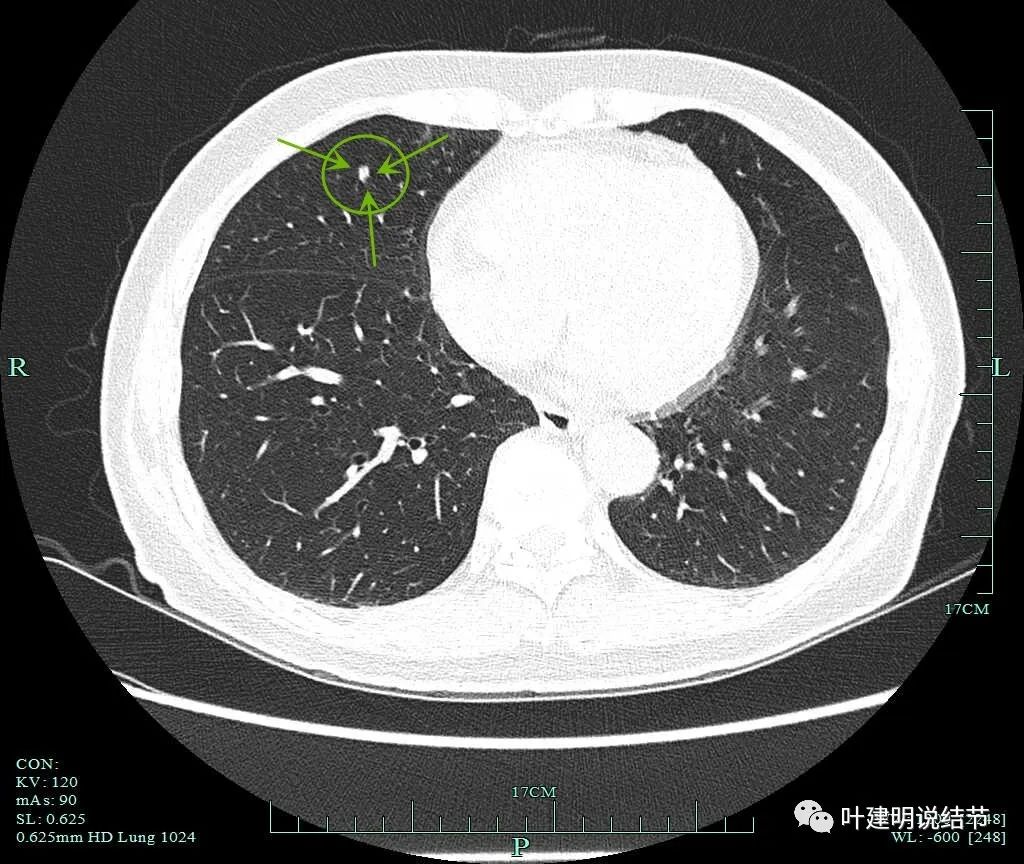

我们手术前做了靶扫描的重建,但当时请影像做的是病灶2、病灶6和病灶8。我的纠结在于中叶这个实性病灶是什么?如果它是炎性的或肺内淋巴结,密度是不是要更高一点?两肺这么多结节都考虑肿瘤范畴,只有这处是炎性或良性的,好像说不大通。我们以前也一直强调:如果多发结节,有的良恶性难定,有的较为明确是恶性,那么难定的也很可能同样的恶性的;有的较为明确是炎性的,那么难定的这处也可能是炎性的,因为致病的因素是一样的。有了这个念头之后,再回头去看中叶的结节,怎么总觉得虽像实性,但不够密实。所以我打电话请影像科同事重新为她中叶这颗也靶重建一下看看细节信息。

病灶9的重建发现不是实性结节,而混合磨玻璃密度。绿色箭头示边上有磨玻璃成分,而且紫色箭头示边缘是毛糙的,红色箭头示整体轮廓是清的。

上图也显示病灶边缘毛糙,不光滑,与胶原结节、淋巴结等良性结节是不符合的。

右肺中叶病灶9考虑是浸润性腺癌,比其他病灶风险都高,它应该是主病灶了。但鉴于两肺多发病灶基本上都考虑肿瘤范畴的,即使此灶考虑浸润性,但毕竟还小,也有磨玻璃成分,存在转移的概率极小,仍应该可以考虑妥协性的楔形切除。